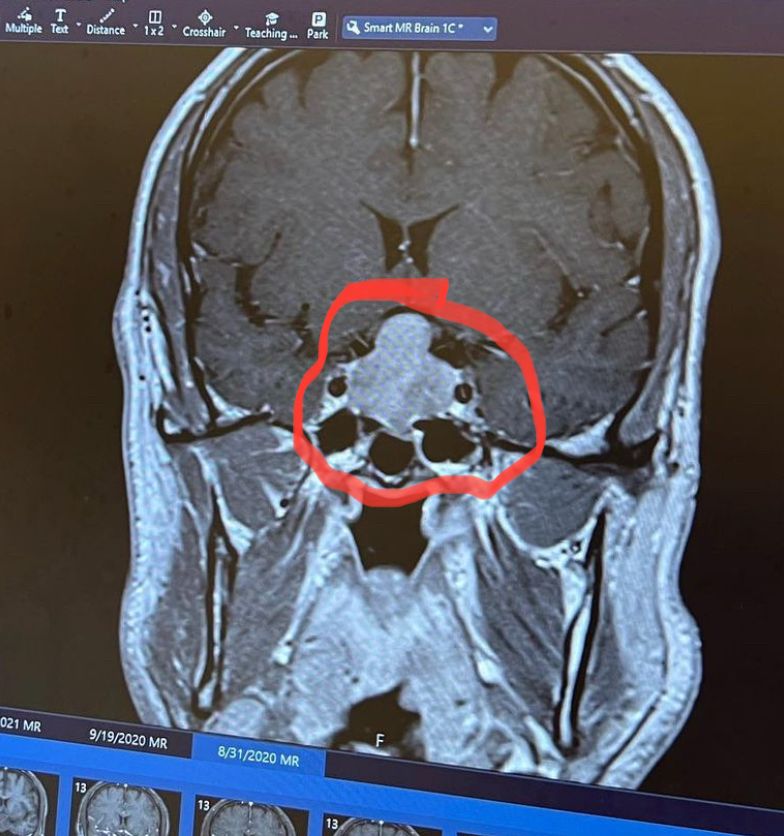

My last Ironman, which marked my 13th race, proved to be a challenging and unexpected journey, as it didn’t unfold as I had hoped. Leading up to the event, I had trained diligently, yet something felt off. Little did I know that I was grappling with a significant health issue: my first brain tumor, which would later explain the struggles I faced during the race. As I crossed the finish line I felt such a bittersweet mix of accomplishment and frustration. From that moment on, Angela (my wife) and I closed the chapter on our Ironman experiences.

4 Brain Tumors Over 14 Years